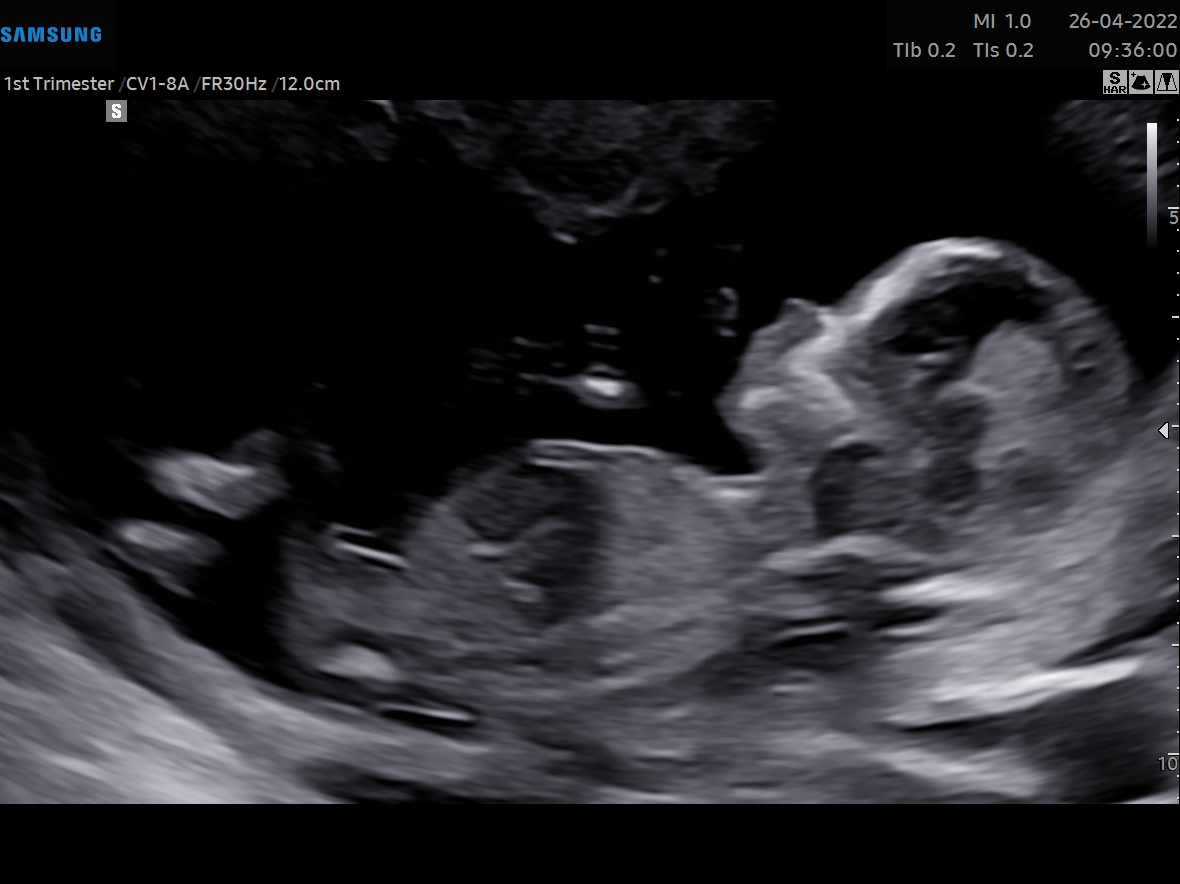

Tricky NUB 13+1 weeks? Long NUB but some stacking?